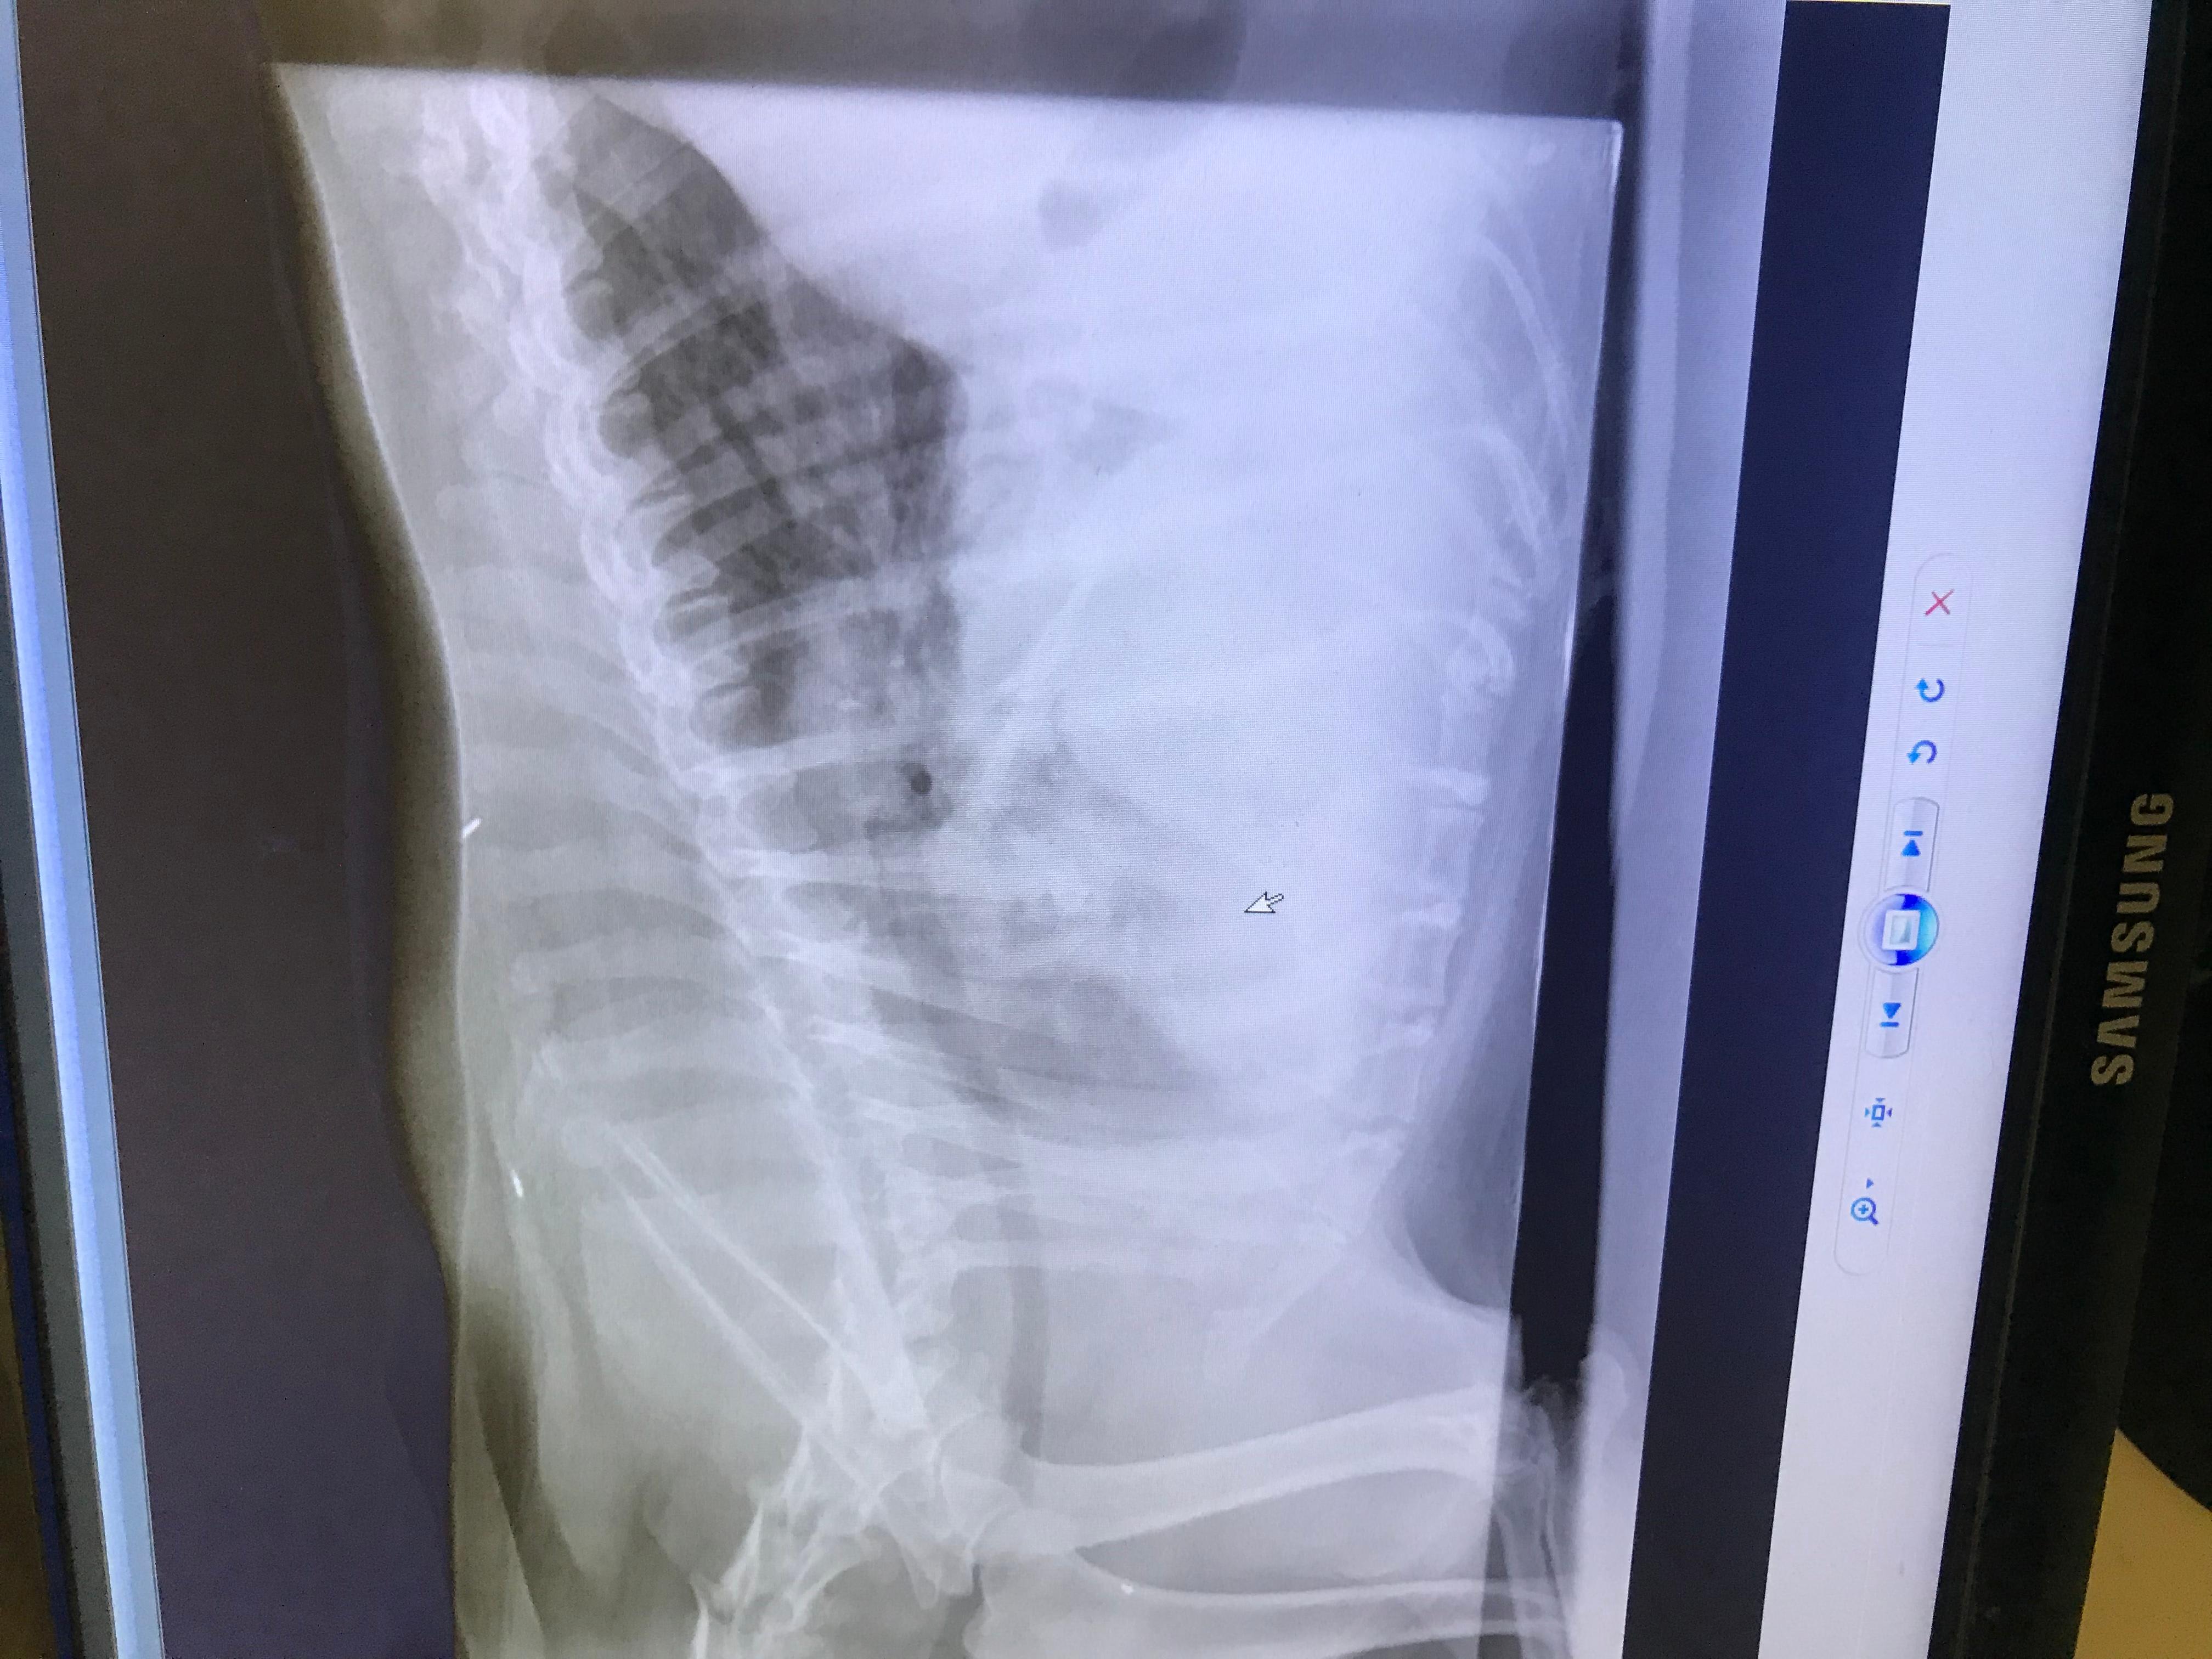

My dog's X-ray shows lung issues. How to tell pneumonia from cancer?

Hi, I’d really appreciate some clarity on some x rays given to me by my vet, she is unable to tell me whether this is pneumonia or lung cancer in my 7 year old rescue Rottweiler Edie Thanks

An X-ray shows abnormalities like those Edie has in her lungs. They do not give a diagnosis. More tests need to be done to determine if this is pneumonia or cancer. They will look at the white blood cell count for infection and they can do cytology on the bronchial discharge to see if it’s infection or if cancer cells are present. If you want you can take Edie to a specialist to complete the additional tests needed to get a definitive diagnosis. Once there is a diagnosis then they can treat her appropriately. Thanks for using Petco Pet Education Center, formerly Petcoach to help you care for Edie.